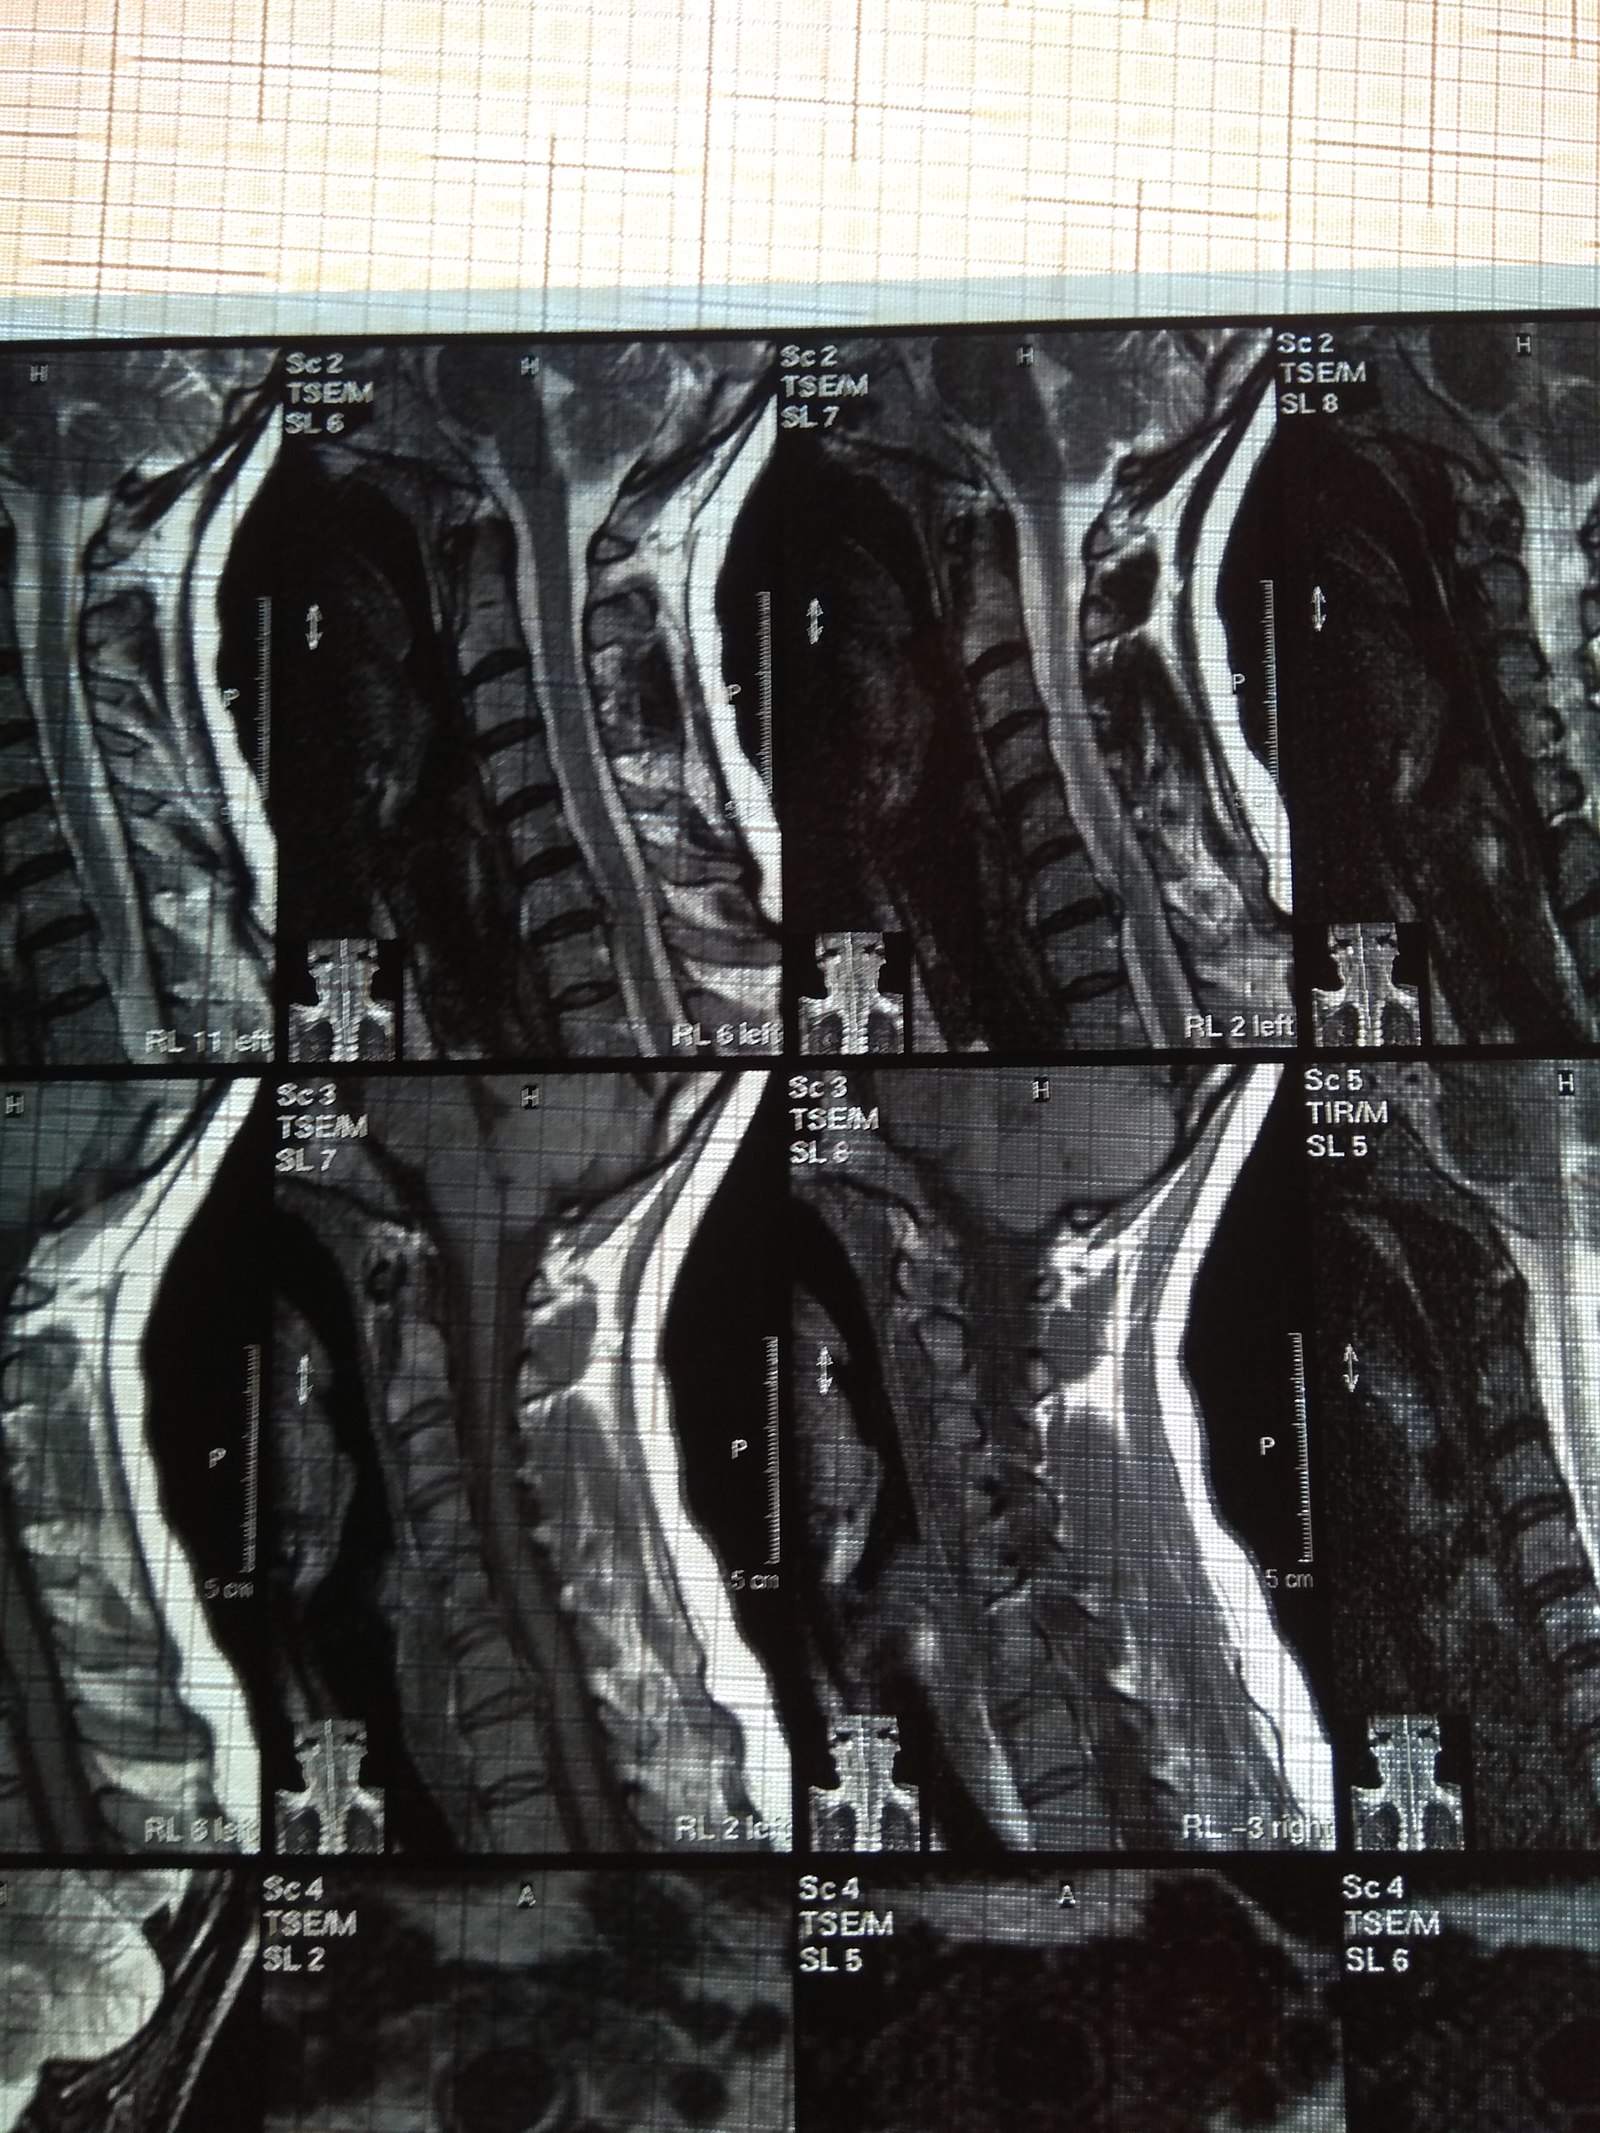

У подруги случилась проблема, тянула с визитом к врачу и в итоге потеряла сознание, вызывали скорую и направили к неврологу. Онемение пальцев на правой руке, сильные боли до судорог и потери сознания. В итоге невролог направил на МРТ и к нейрохирургу, выписали ношение ортопедического воротника, 2 вида уколов и таблетки, названия навскидку не помню. Сказали если через 10 дней не полегчает, то на операцию. Сегодня 5й день, никаких улучшений, рука с каждым днем выше немеет, но подвижность пока в норме. В день по 2-3 раза колет кетонал. Я вот переживаю как бы рука не отказала. Такое может случиться?